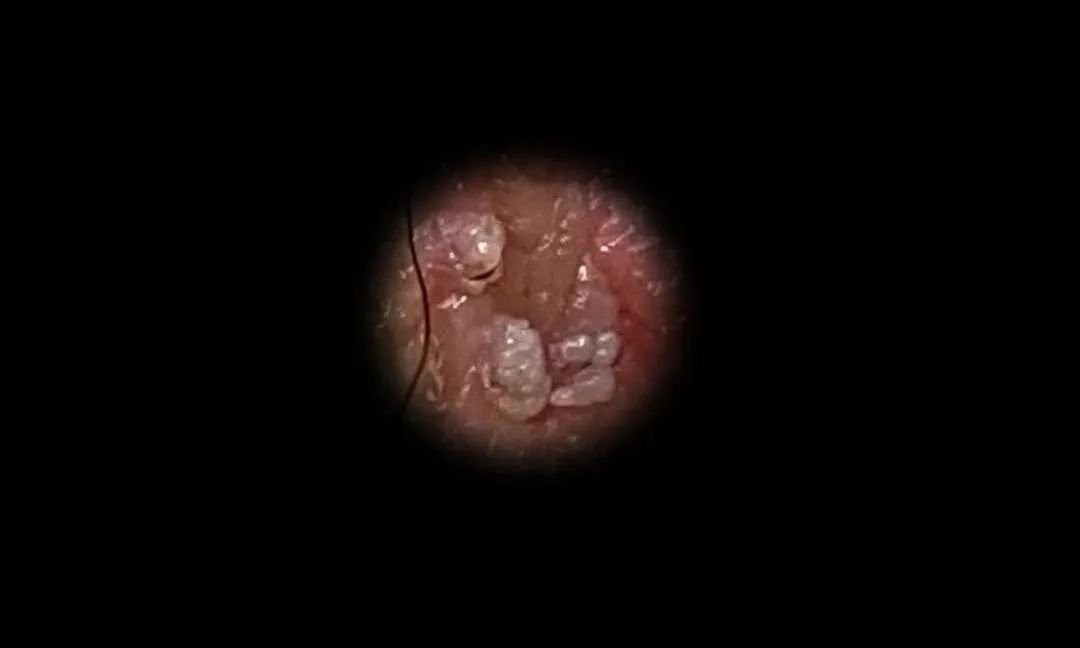

尖锐湿疣晚期的症状是疣体会继续生长、数量增加。还可以在患者阴部出现大小不同的乳头状、鸡冠状、鹅卵石状等皮赘,而且会越长越大并相互融合,并可以生长成巨大的尖锐湿疣体。患者阴部经常有瘙痒和压迫感,如果与细菌感染相结合,可能会有恶臭味。邻近组织和器官也会受到疣体的压迫。